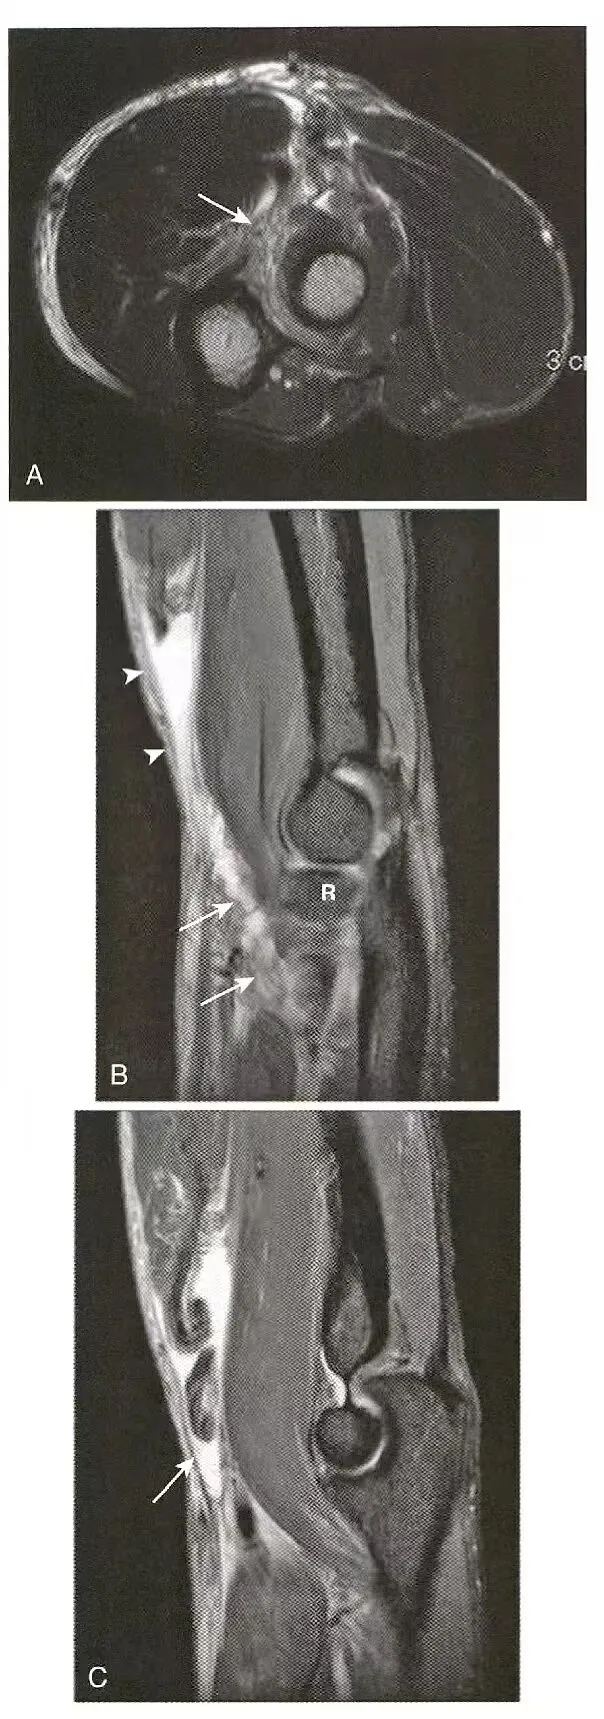

肌腱全层撕裂:  A,肱二头肌腱远端未出现在正常走行的位置, B,在肌腱的位置有明显的积液,近端有高信号积液或出血, C,增厚、撕裂的肱二头肌腱在其附着部位向上回缩数厘米。